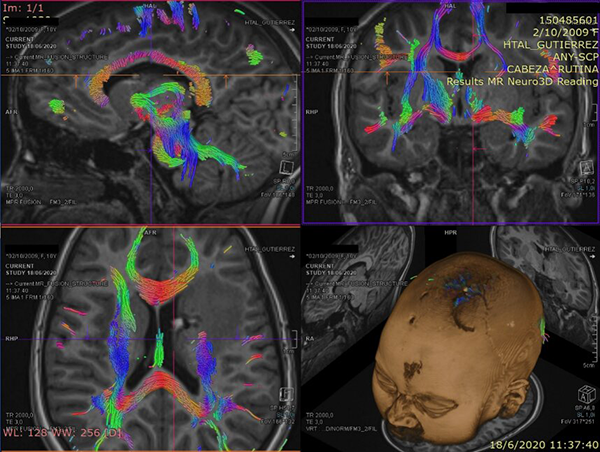

La paciente de 12 años presentó cefaleas, hemiparesia y pérdida de conciencia aguda que requirió soporte de Asistencia Respiratoria Mecánica durante tres días, dos meses previos a la cirugía. Debido al volcado ventricular se colocó un Drenaje Ventricular al exterior. Luego del episodio agudo la paciente se recuperó sin déficit motor. Mediante Resonancia Magnética por Imágenes (RMI) se diagnosticó un Cavernoma adyacente a la CI y sobre el Núcleo Caudado (NC) (Figura 1 A, B y C). El estudio de la RMI por Tensor de Difusión (Tractografía) expuso que la vía motora izquierda no estaba interrumpida completamente, quizá desplazada hacia lateral respecto de la rodilla de la CI (Figura 2).

Figura 2: Estudio de Tensor de difusión. Nótese la atenuación de la señal del haz motor en el hemisferio izquierdo.